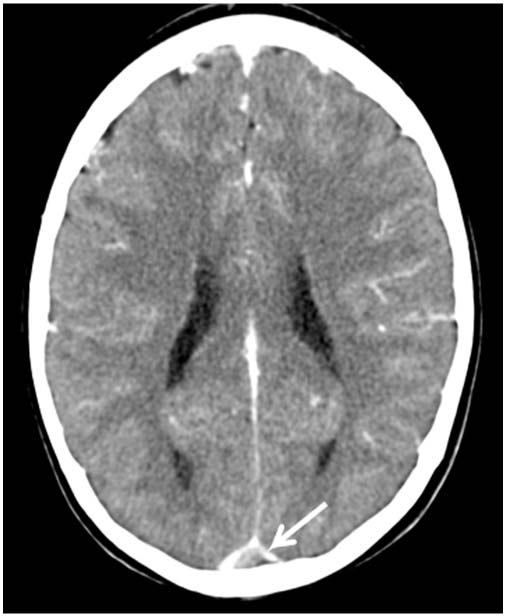

Delta Sign In Ct / Aug 26, 2008 · the empty delta sign is a ct sign of dural venous sinus thrombosis of the superior sagittal sinus, where contrast outlines a triangular filling defect, which represents thrombus.

Filling defect in the right internal jugular vein and sigmoid sinus.